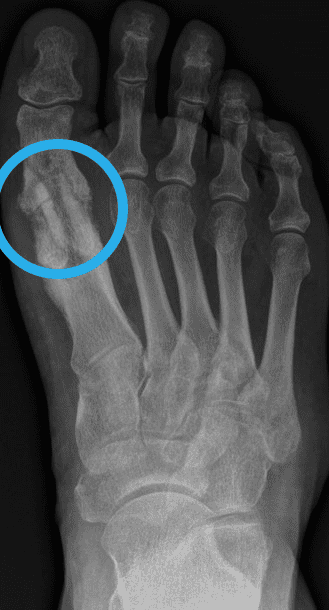

Was ist eine Pseudarthrose? Wenn es 6 Monate nach einem Bruch nicht zur Heilung des Knochens gekommen ist, spricht man laut Definition von einer Pseudarthrose. Zur Heilung werden bei Operationen in der Regel Schrauben aus menschlichem Knochen verwendet. Das Wort Pseudarthrose stammt aus dem Griechischen, wobei „pseudos“ falsch bedeutet und „arthros“ Gelenk. Eine Pseudarthrose ist auch unter den Namen Pseudogelenk oder Scheingelenk bekannt. Pseudarthrosen treten immer nach einem Knochenbruch oder einer Knochenoperation auf, wenn der Knochen nicht richtig verheilt, die Knochenstücke nicht zusammenwachsen. Solange der Knochen nicht vollständig geheilt ist, kann er auch nicht richtig belastet werden. „Auslöser einer nicht heilenden Fraktur ist meist eine zu frühe Belastung, aber auch Entzündungen und Infektionen können den Knochenheilungsprozess einschränken. Der Knochen wächst nach einem Bruch nicht zusammen und in der Folge entsteht die Pseudarthrose.“ So der Experte aus Linz, Dr. Klaus Pastl. Pseudarthrosen können an jedem Knochen, der nicht verheilt, auftreten, egal ob es sich um eine nicht heilende Mittelfuß- Operation, eine fehlgeschlagene Hallux rigidus Operation oder eine nicht heilende Operation nach einem Kahnbeinbruch handelt. Tritt eine Pseudarthrose auf, muss diese behandelt werden.

Symptome einer Pseudarthrose

Ein eindeutiges Anzeichen einer Pseudarthrose ist, wenn die Knochenbruchenden innerhalb von 4 – 6 Monaten nicht stabil zusammengewachsen sind. Weitere typische Symptome einer Pseudarthrose sind Rötungen, Schmerzen und Schwellungen über dem nicht geheilten Knochenbereich. „Da durch die Pseudarthrose die Stabilität des Knochens stark beeinträchtig ist, treten häufig Fehlstellungen, Bewegungseinschränkungen, Gelenksprobleme aber auch Muskelschwund in der betroffenen Region auf.“, erklärt Dr. Klaus Pastl, Orthopäde aus Linz. Bei den meisten Betroffenen treten Schmerzen anfangs nur bei Bewegung und Belastung auf. Schreitet die Pseudarthrose fort, treten die Schmerzen und Symptome aber auch in der Ruhephase auf. Tritt eine Pseudarthrose nach einer Implantation von Metallschrauben oder Metallplatten auf, ist ein zu spätes Reagieren besonders gefährlich. Heilt der Knochen nicht rechtzeitig, lastet das gesamte Gewicht auf den Metallplatten und Metallschrauben. Diese können durch die Belastung brechen. „Gebrochene Metallteile im Körper können äußerst schmerzhaft für Patienten sein. Auch für den Chirurgen sind diese Operationen äußerst unangenehm und schwierig. „Operationen sind mühsam und komplex. Oft muss viel Knochen zerstört und die umgebenden Weichteile verletzt werden, um die gebrochenen Metallteile aus dem Knochen des Patienten zu bergen. Manchmal können nicht alle Metallteile entfernt werden und müssen dann im Knochen verbleiben. Das ist frustrierend, für Patienten und Chirurgen.“

Wie wird eine Pseudarthrose diagnostiziert?

Die Diagnose einer Pseudarthrose wird über Röntgenbilder gestellt. Bei unklaren Röntgenbefunden kann auch eine Computertomographie (CT) oder Kernspintomographie (MRT) sinnvoll sein.